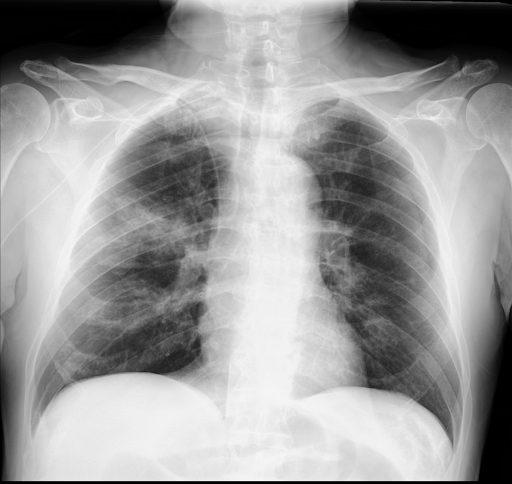

Bildgebung:

Im Röntgenbild zeigen sich rechtsbetonte, bilateral konfluierende Infiltrate. Im CT des Thorax zeigen sich apikal betonte bronchiozentrische Konsolidierungen mit milchglasartigen Verdichtungen und Bronchialwandverdickungen.